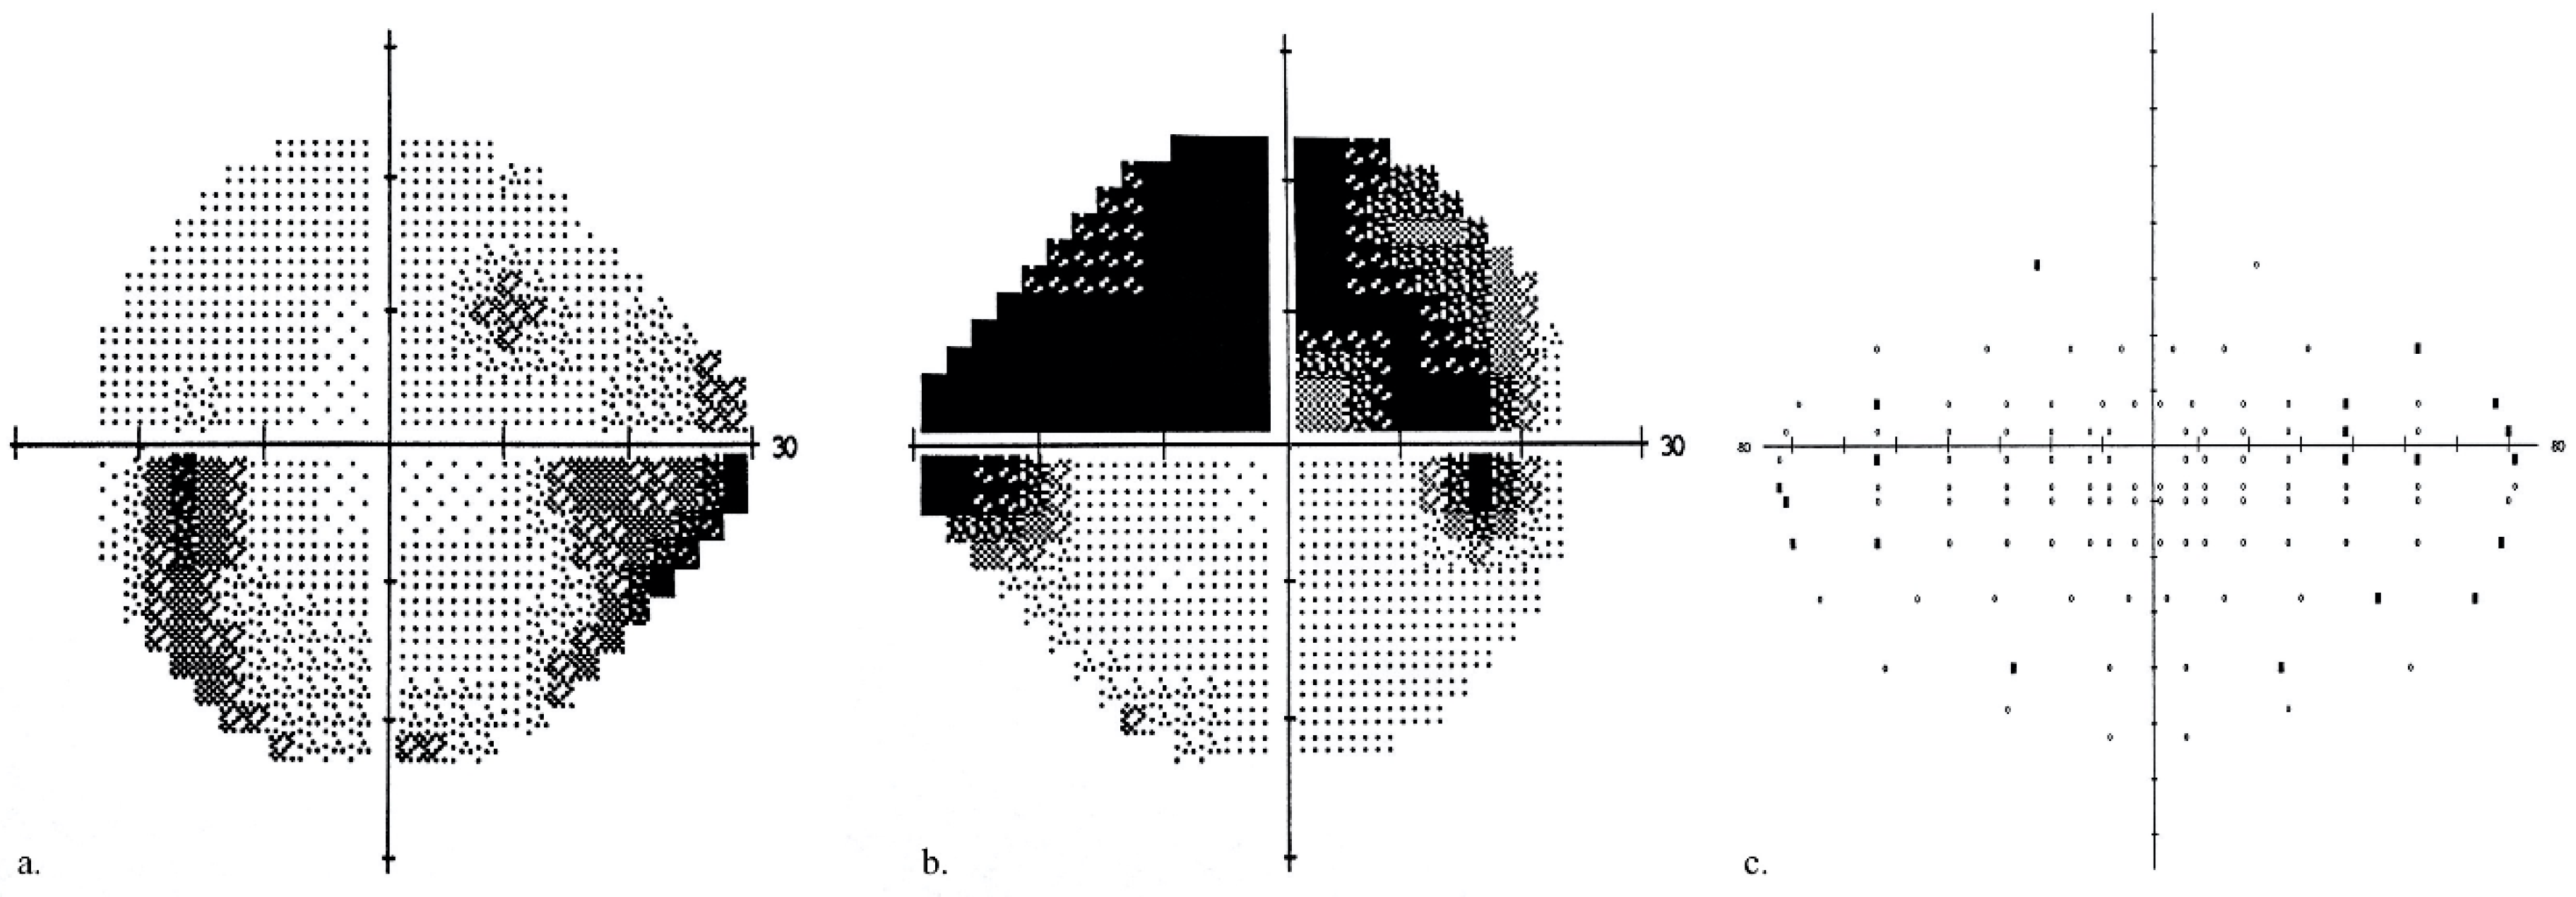

All participants underwent best-corrected visual acuity (BCVA) assessments using a Snellen chart, perimetry (Humphrey Field Analyzer, Carl Zeiss Meditec, Inc., Dublin, CA, USA), and 24-2 Swedish interactive threshold algorithm (SITA)-standard VF testing. Mean deviation (MD) scores were recorded for each eye. A binocular VF score was generated by binocular Humphrey Esterman Visual Field (HEVF). In the HEVF, a grid of 120 test points with light intensity of 10 dB was used to examine more than 130° of the VF. Binocular VF defects with a number of omitted (unseen) points and Esterman coefficients were analyzed. Eyes were classed as “better” or “worse” eye based on the MD score. Inter-eye differences in the MD were calculated and an inter-eye difference of >5 dB was used as the threshold for MD asymmetry. An example of a VF defect is presented in Figure 1.

Figure 1.

Example of a visual field defect in a glaucoma patient (gray scale): (a) left eye MD of −4.79 dB, (b) right eye MD of −14.64 dB, (c) binocular VF defect of 20 (out of 120), and a Esterman coefficient score of 83.